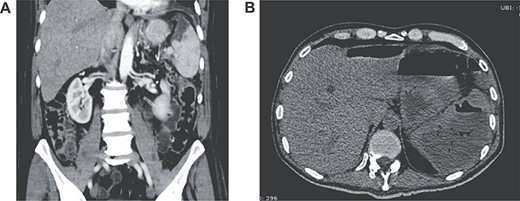

Two weeks after discharge, he developed a high fever and acute abdominal pain in his upper left abdomen. Diffuse abdominal tenderness was detected and complementary exams revealed leukocytosis, neutrophilia, elevated C-reactive protein and increased levels of serum procalcitonin. Attributable to his background, a contrast-enhanced abdominal CT was requested detecting an enlarged spleen with a hypodense low-density lesion filled with gas. Free liquid was detected in the abdomen as well (Fig. 2A and B).